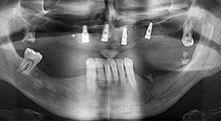

Bratu: Utilizamos los insertos de forma rutinaria para la extracción de injertos óseos y la ranuración de las crestas alveolares. También utilizamos las Piezomed B6/B7 para practicar osteotomías en dientes retenidos y no retiramos implantes que pueden conservarse. Todas estas son indicaciones que requieren cortes profundos y limpios.

Bratu: Preferimos realizar las osteotomías en la línea oblicua externa de la cara posterior del maxilar inferior, y no en la región situada entre los orificios. Tras realizar una incisión en los tejidos blandos, utilizamos las nuevas sierras para definir el contorno de la osteotomía. De este modo, conseguimos una preparación completa en prácticamente el 80 por ciento de los casos. Por otro lado, en algunas ocasiones también utilizamos otros insertos piezoquirúrgicos, así como un cincel para mover el injerto. Para nosotros, esta es una técnica de intervención muy eficaz.

Bratu: Nos gusta utilizar la técnica de sándwich para realizar aumentos en la cara lateral del maxilar inferior. En este procedimiento, se utiliza la sierra piezoquirúrgica para preparar una tapa ósea, mientras que el fragmento crestal se fija con microtornillos. Entre medias, colocamos una combinación de hueso autólogo y material óseo adicional xenógeno. Y con ello obtenemos un rendimiento muy fiable. Asimismo, en los ranurados de la cresta alveolar del maxilar inferior, nunca se puede prescindir de cortes verticales suficientemente dimensionados, pues, de lo contrario, los huesos pueden fracturarse fácilmente.